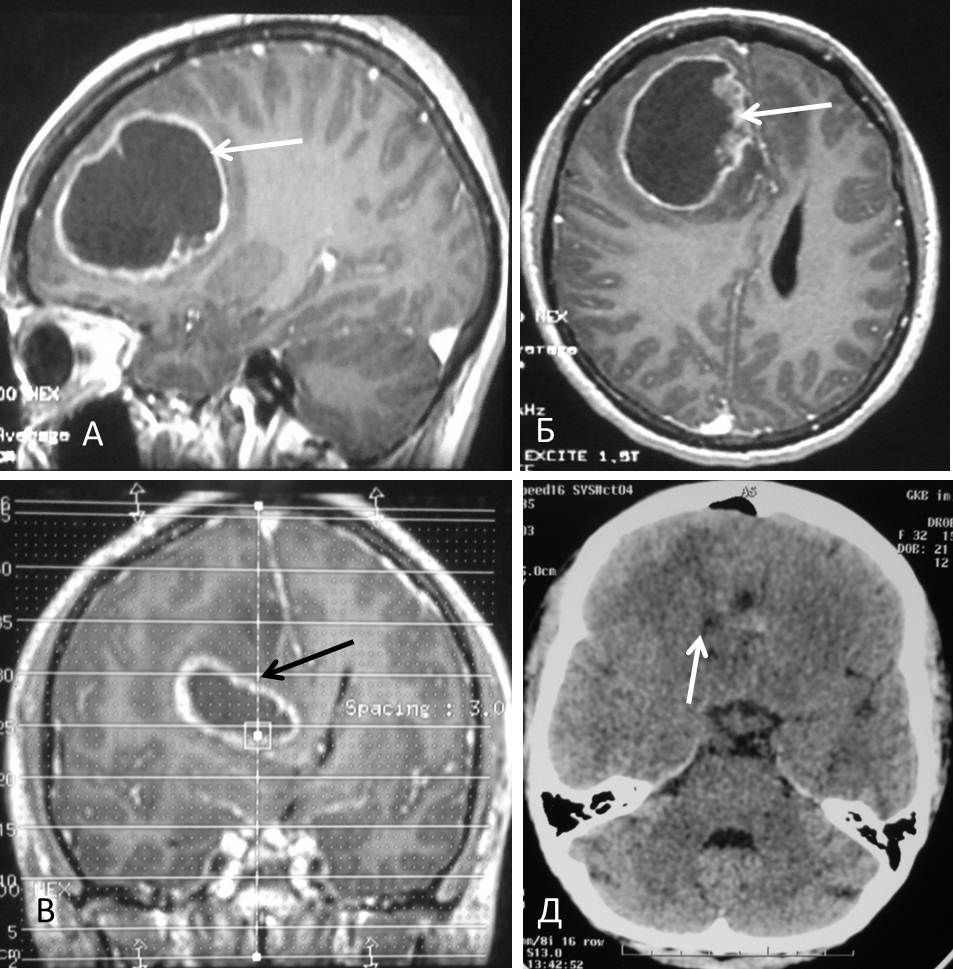

Для глиобластом характерно беспорядочное скопление клеток опухоли с увеличенным количеством ядер, которые перемежаются с очагами некроза и измененных сосудов.

Данный вид злокачественного образования, появляющегося в головном мозге, очень опасен по причине быстрого роста и отсутствия четких разграничений между пораженными и здоровыми тканями.

Мультиформная глиобластома — наиболее опасная форма с наличием очагов некроза. Кроме поражения клеток, происходит быстрое прогрессирование некротических процессов в сосудах. Это провоцирует страшные и необратимые последствия.

- МРТ мозга, КТ с контрастным веществом. Эти способы помогают установить локализацию опухоли, обширность распространения.